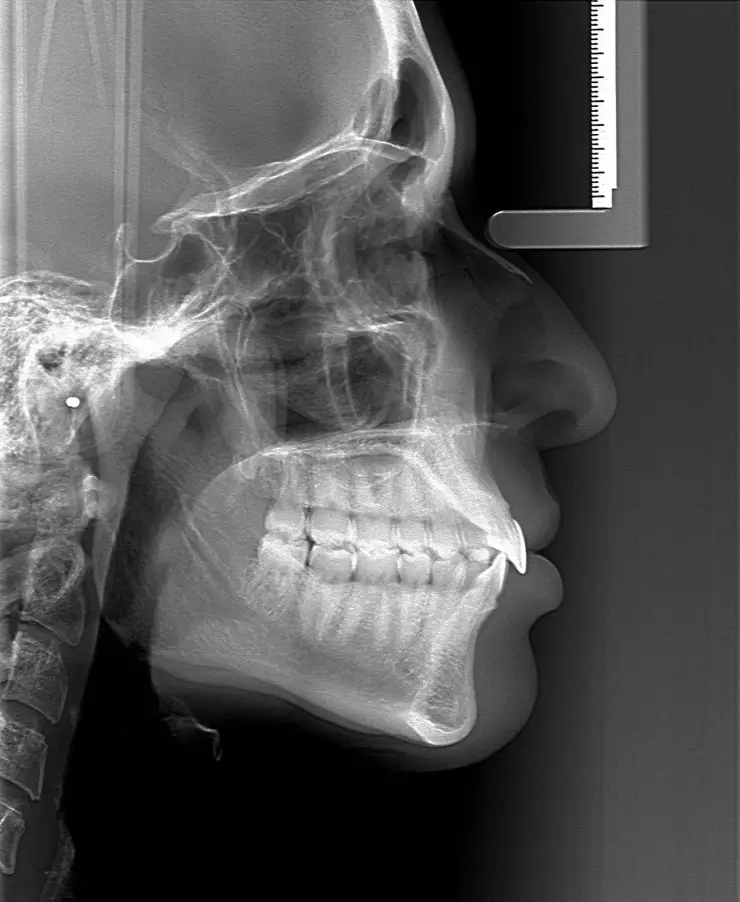

Cephalometric X-ray (ฟิล์มกะโหลกศีรษะด้านข้าง)

- เป็นการถ่ายภาพด้านข้างของศีรษะและขากรรไกร

- จะช่วยให้ทันตแพทย์เห็นโครงสร้างกระดูกขากรรไกร มุมของฟันหน้าบนและฟันหน้าล่าง

- ช่วยประเมินว่าควรมีการถอนฟันก่อนจัดฟันหรือไม่

การถ่าย Cephalometric X-ray ทำให้ทันตแพทย์เห็นภาพของกระดูกขากรรไกรในมุมด้านข้างอย่างชัดเจน ทันตแพทย์จะได้เห็นว่าขากรรไกรบนและล่างมีตำแหน่งหรือรูปทรงที่ผิดปกติหรือไม่ นอกจากนั้นหากตรวจแล้วพบว่ามีปัญหาด้านการสบฟันที่ผิดปกติ ทันตแพทย์ก็จะสามารถวางแผนการจัดฟันหรืออาจจัดฟันร่วมกับการผ่าตัดขากรรไกรได้ดีขึ้น

2.2 ประเมินมุมของฟันหน้า

จาก Cephalometric X-ray ทันตแพทย์จะได้เห็นว่าฟันหน้าบนและฟันหน้าล่างมีลักษณะยื่นหรืองุ้มขนาดไหน ซึ่งจะช่วยให้ตัดสินใจได้ว่าควรจะต้องถอนฟันร่วมกับการจัดฟันเพื่อให้มีช่องว่างสำหรับเคลื่อนฟันหรือไม่ รวมถึงเลือกเครื่องมือจัดฟันร่วมกับคนไข้ว่าจะจัดฟันแบบไหน